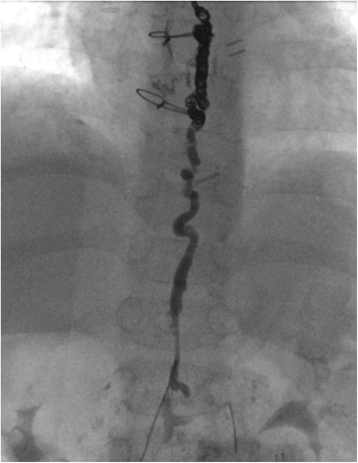

Fig. 3From: Case report description of a collaborative approach to thoracic duct embolization in patients with congenital heart diseasePost intervention demonstrates coils and contrast occluding the TDBack to article page